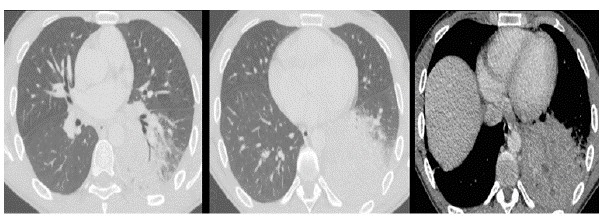

Desde el momento de consulta inicial hasta completar los exámenes ordenados trascurrió un año, por lo que se realizó control tomográfico de la lesión y en el que se evidenció aumento del tamaño de la lesión, que medía ahora 50 x 22 x 34 mm, y se evidenciaba un vaso sistémico procedente del tronco celiaco, estableciéndose el diagnóstico de un posible secuestro pulmonar.

La paciente fue llevada a videotoracoscopia derecha, la que ratifica la presencia de un vaso arterial sistémico aberrante, procedente del abdomen y una lesión pulmonar bien delimitada en el segmento posterior del lóbulo inferior derecho, que estaba en contacto con dicho vaso arterial. Se procede entonces a ligadura del vaso arterial con sutura mecánica y posterior segmentectomía no anatómica del segmento posterior del lóbulo inferior derecho (figura 4).